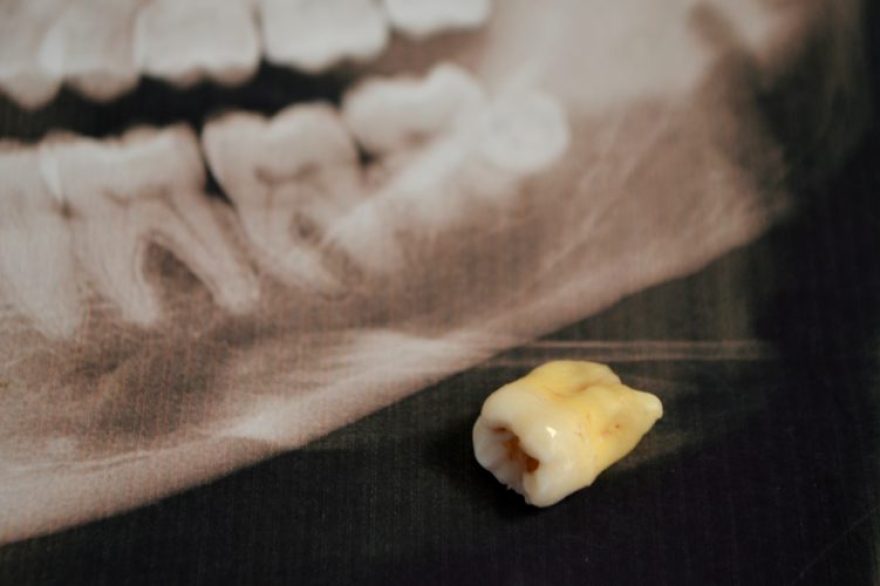

Extraction

Given the potential problems and complications associated with wisdom teeth, extraction is often recommended when issues arise. Extraction is typically performed by an oral surgeon or dentist and involves the removal of one or more wisdom teeth.

Removing wisdom teeth can prevent the common complications associated with them, such as damage to other teeth and shifting them out of alignment, and can provide relief from the pain and discomfort associated with emerging wisdom teeth.